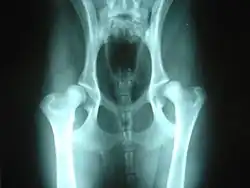

Röngenfoto van gezonde heupen